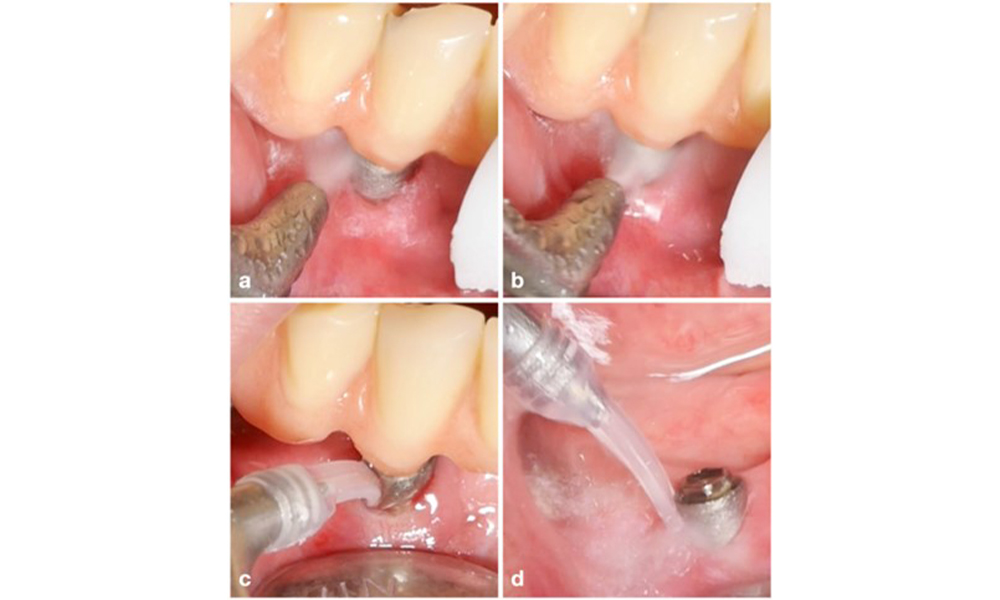

The choice of equipment depends on clinical circumstances, such as the distinction between calculus and soft plaque. Thus, in cases with calculus, titanium or plastic curettes, or specially designed tips for ultrasonic scalers should be used first, followed by the use of an air-polishing device (figure 7). In cases with only soft plaque accumulation, an air-polishing device alone can be sufficient. Air-polishing devices are operator and patient friendly and at least as efficient as standard instruments (Schwarz et al. 2015a).

Management of peri-implantitis at implants judged as treatable consists of a non-surgical phase, which is often followed by surgical intervention. For the non-surgical approach, similar measures as those applied for the treatment of peri-implant mucositis are used; based on laboratory experiments air-polishing devices with a subgingival nozzle appear to provide certain advantages in terms of biofilm removal, compared to hand- or ultrasonic instruments (Herrera et al. 2023; Moharrami et al. 2019; Ronay et al. 2017) (figure 9).